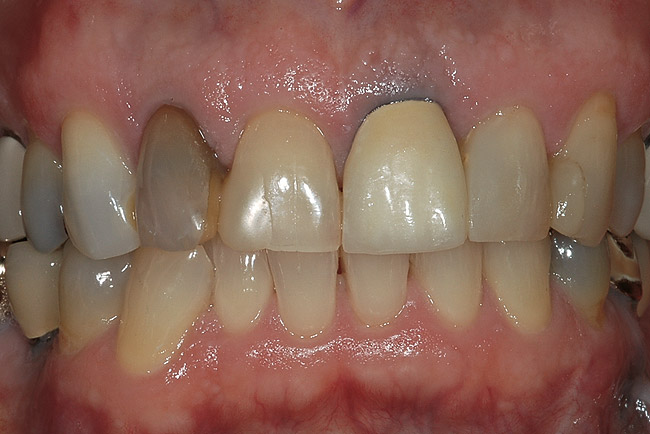

Figure 1  A clinical examination demonstrates a single, very dark lateral incisor and a moderately dark central incisor with a crown on the adjacent central incisor and several dark gingival areas.

Figure 1

The first and most important consideration is to determine the cause of the tooth discoloration. A clinical examination is conducted, which includes evaluation of the color of the teeth and the adjacent gingiva (Figure 1). Additionally, transillumination, radiographs, and pulp testing may be appropriate. Radiographs should always be taken of a single dark tooth, as teeth can undergo pulpal necrosis without any other symptom than becoming dark (Figure 2). From this examination, the determination is made of whether the tooth is vital or not. A vital tooth may be darker due to trauma and resultant bleeding into the dental tubules without loss of vitality. Vital teeth may also discolor from internal or external resorption, calcific metamorphosis, as well as decay or leaking restorations on the proximal or lingual surfaces. A non-vital tooth may have become darker from the same reasons as a vital tooth, but also have experienced pulpal death. A tooth that has received endodontic treatment may also later darken, especially if there is a poor seal of the endodontic access opening (Figure 3).

Additional considerations for the single dark tooth are the color of the gingival tissues around the tooth, as well as whether there is any root structure visible due to recession. A smile analysis is used to determine these conditions as well as the movement of the lip during smiling and whether a “gummy smile” exists. The dentin in the root is different from the dentin in the anatomic crown, and does not bleach well if at all, regardless of whether internal or external bleaching is attempted. Also, discolorations of the gingiva may cause a tooth that may be a perfect color match to not be harmonious. Either of these conditions is magnified if the lip exposes much of the root or gingiva because of a hyperactive lip or gummy smile.